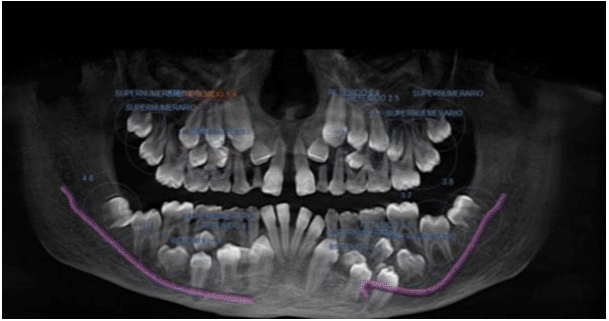

Radiographic studies including posteroanterior (PA) and lateral skull radiographs, PA chest radiograph, PA and lateral spine radiograph, and maxillary tomography were obtained (Figure 1).

Following radiographic evaluation, the characteristic cleidocranial dysostosis triad—supernumerary teeth, total or partial clavicular agenesis, and cranial alterations—was evident (Figure 2 & 3).

As per Tanaka et al.8 the diagnostic triad for cleidocranial dysostosis encompasses the complete or partial absence of clavicles, supernumerary teeth, and cranial anomalies including dysostosis of cranial sutures, failure of fontanelle closure, incomplete formation of the facial skeleton, and the absence of frontal and maxillary sinuses.